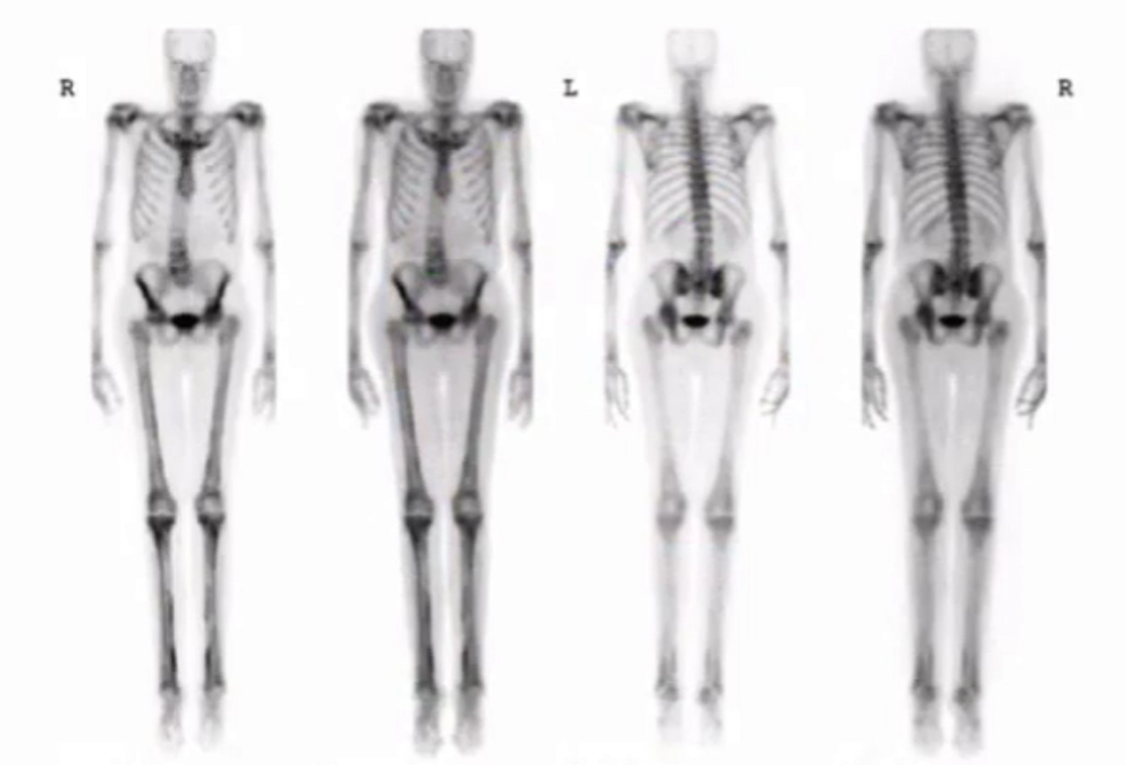

Normal kid

• Uptake in epiphysis in kids - normal